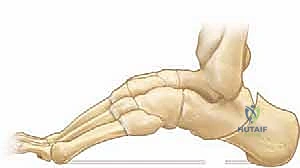

القدم الجوفاء عند الأطفال هي تشوه يتميز بقوس قدم مرتفع بشكل غير طبيعي. تهدف الجراحة التصحيحية إلى استعادة وظيفة القدم وتوازنها، وتشمل تحرير الأنسجة الرخوة، وتعديل الأوتار، وإجراء قطع العظم لتصحيح التشوه، مما يضمن قدمًا متحركة ومستوية.

الخلاصة الطبية السريعة: القدم الجوفاء عند الأطفال (Pediatric Cavus Foot) هي تشوه هيكلي وعصبي عضلي معقد يتميز بقوس قدم مرتفع بشكل غير طبيعي، حتى أثناء الوقوف وتحمل الوزن. تهدف الجراحة التصحيحية المتقدمة إلى استعادة وظيفة القدم، وتصحيح التوازن العضلي، ومنع التدهور المستقبلي للمفاصل. تشمل الإجراءات الجراحية تحرير الأنسجة الرخوة، ونقل الأوتار، وإجراء قطع العظم (Osteotomy) لتصحيح التشوه ثلاثي الأبعاد، مما يضمن للطفل قدمًا مستوية ومستقرة وخالية من الألم.

تُعد القدم الجوفاء عند الأطفال إحدى أكثر حالات تشوهات العظام تعقيدًا في مجال جراحة عظام الأطفال. لا يقتصر تأثير هذه الحالة على المظهر الخارجي للقدم، بل يمتد ليؤثر بشكل جذري على الميكانيكا الحيوية لحركة الطفل، وقدرته على المشي، ومشاركته في الأنشطة الرياضية واليومية. تتميز هذه الحالة بارتفاع مفرط في القوس الطولي للقدم، مما يؤدي إلى تركز وزن الجسم بالكامل على الكعب ومقدمة القدم (رؤوس الأمشاط)، متجاهلًا منتصف القدم الذي من المفترض أن يمتص جزءًا كبيرًا من صدمات المشي.

لفهم مشكلة القدم الجوفاء، يجب أولاً فهم الهندسة المعمارية للقدم البشرية. تتكون القدم من 26 عظمة، و33 مفصلًا، وشبكة معقدة من أكثر من 100 وتر وعضلة ورباط. تعمل هذه المكونات معًا لتشكيل ثلاثة أقواس رئيسية (قوسان طوليان وقوس عرضي) تعمل كنوابض لامتصاص الصدمات وتوزيع وزن الجسم.

في حالة القدم الجوفاء (Cavus Foot)، يحدث خلل في التوازن العضلي، غالبًا ما يكون ناتجًا عن ضعف في العضلات الجوهرية للقدم مقابل نشاط مفرط للعضلات الخارجية (مثل العضلة الظنبوبية الخلفية والشظوية الطويلة). يؤدي هذا الخلل إلى:

1. انثناء أخمصي في المشط الأول (Plantarflexed First Ray): مما يدفع القوس للارتفاع.

2. انقلاب الكعب للداخل (Hindfoot Varus): مما يقلل من مساحة التلامس مع الأرض ويسبب عدم استقرار الكاحل.

3. أصابع المطرقة أو المخالب (Claw Toes): نتيجة الشد المستمر للأوتار الباسطة والقابضة.